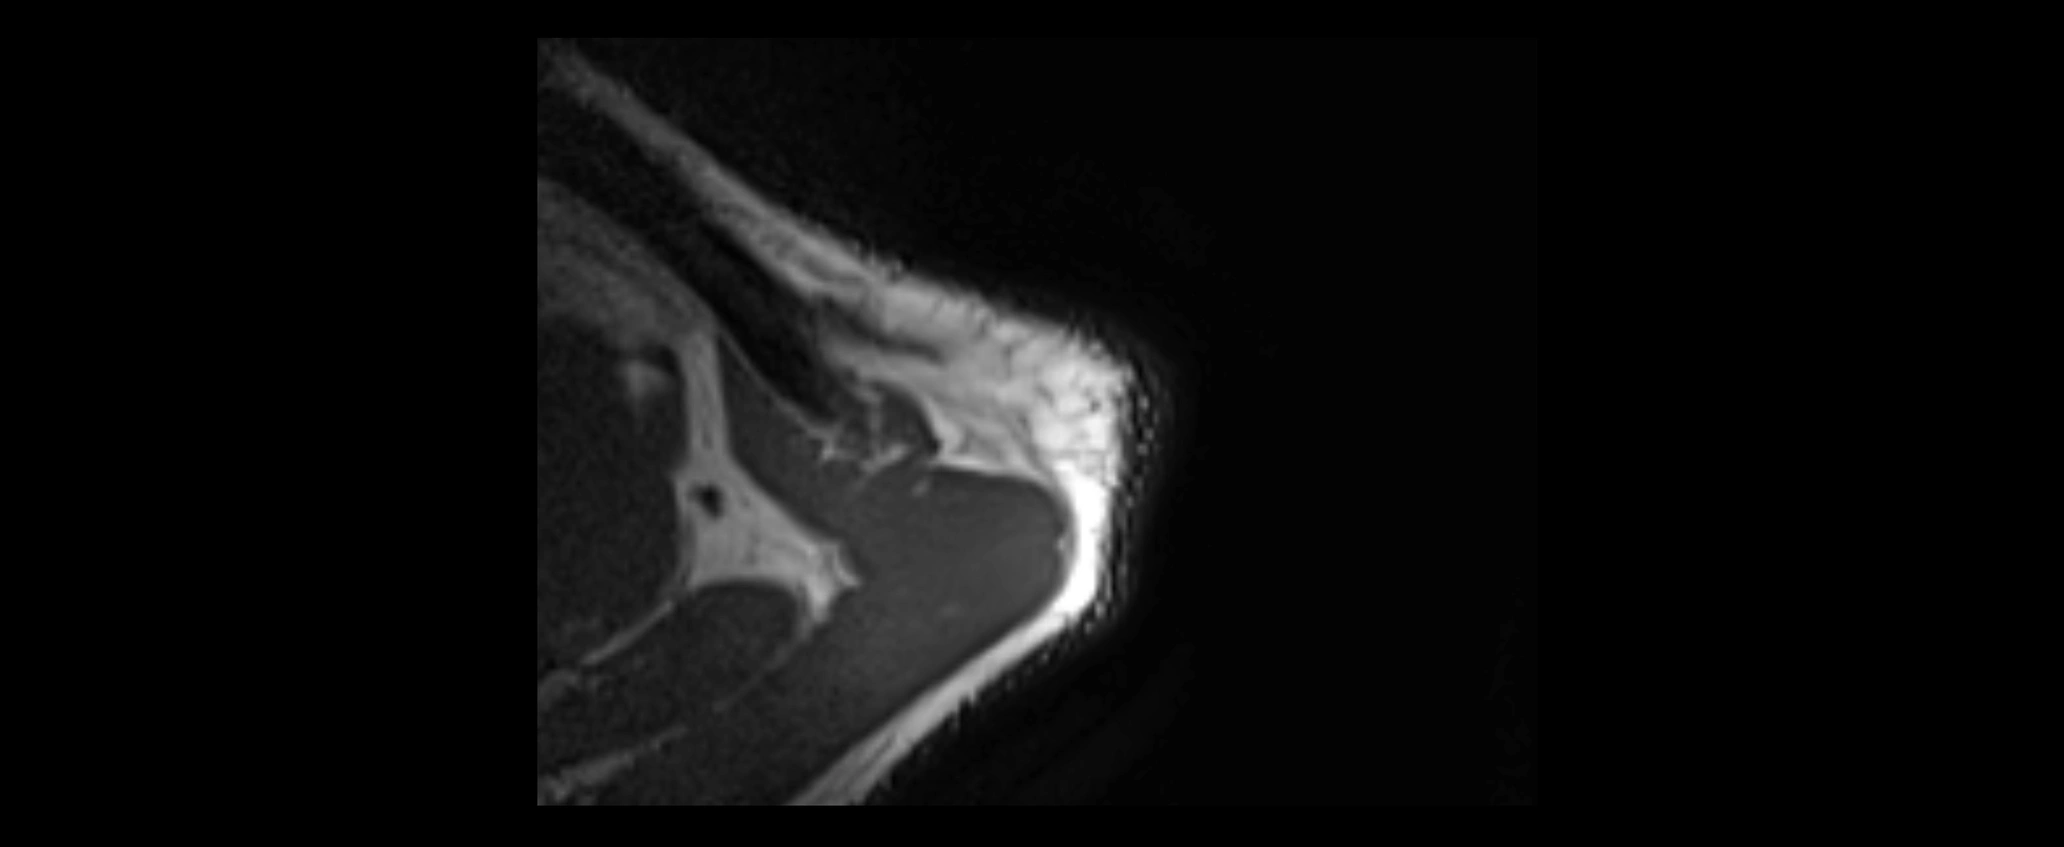

CT image

image